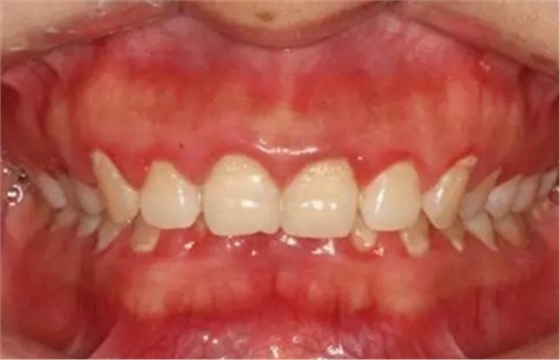

(1)檢查牙齦色澤、形態(tài)和質地的變化,用文字描述。

(2)用指數(shù)記分法如牙齦指數(shù)(GI)、齦溝出血指數(shù)(SBI)等量化指標來記錄牙齦的炎癥程度。